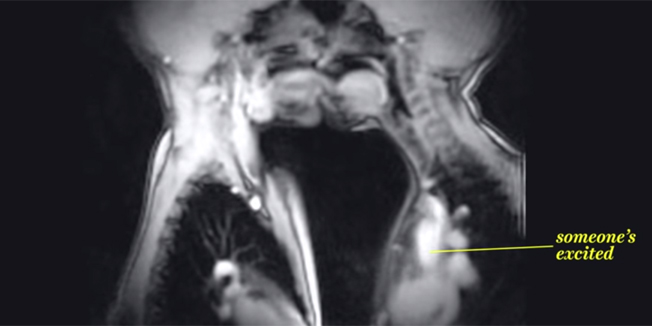

VIDEO: OVAKAV SEKS NIKAD PRIJE NISTE VIDJELI Zapanjujući pogled iznutra na omiljenu ljudsku aktivnost

Za razliku od rentgena, skeniranje magnetskom rezonancom (MRI) nema nikakve štetne posljedice po ljudsko tijelo, pa je moguće stvarati videosnimke procesa koji se odvijaju unutar ljudskog tijela.

Na snimkama se vide molekule vode, koja je prisutna u svim tkivima ljudskog organizma, no u različitim postocima, što omogućava MRI skeneru da različita tkiva prikazuje različitim bojama.

Osim što je tehnika MRI snimanja izrazito korisna za otkrivanje zloćudnih bolesti i pripreme pacijenata za kirurgiju, doprinosi znanosti i kroz nevjerojatan pogled na unutrašnjost organizma čovjeka.

U ovom kratkom, edukativnom videu koji je kompilirao portal Vox, možemo vidjeti kako ‘iznutra’ izgledaju neke normalne životne funkcije, poput govora, sviranja, disanja, ljubljenja, pa čak i seksa...